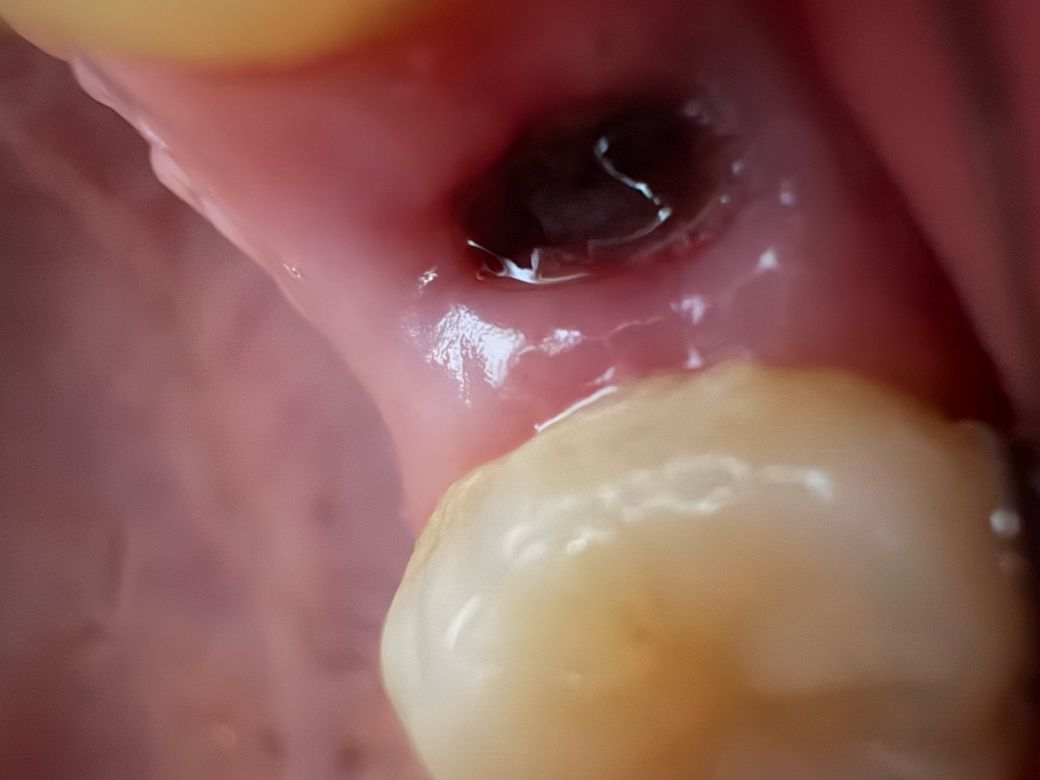

위쪽 소구치 발치 후 5일차 드라이소켓 가능성

화요일 낮에 발치하고 오늘로 5일차입니다. 담배는 발치 후 이틀 뒤부터 하루에 한 개비 정도로만 폈고 오늘 마셔야 될 일 있어서 맥주 한 캔 분량 마셨더니 구멍이 조금 시렵습니다. 아주 살짝 아픈 것도 같아서 확인해봤는데 혹시 이거 드라이소켓 전조증상인가요?

사진상으로 잘 아물고 잇는거 같습니다. 아직 상처가 아물지 않아서 그러는거니 걱정하지 않으셔도 될것같습니다.

사진상 드라이소켓의 양상은 아니지만 발치 후 음주, 흡연으로 인해 드라이소켓 발생 가능성이 높아지므로 걱정된다면 1~2주는 피하세요